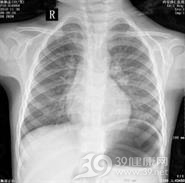

X线检查:肺部散在的片状模糊阴影,段性和亚段性分布,有时呈大叶性实变征象,多数发生在一侧或双侧肺部下叶。